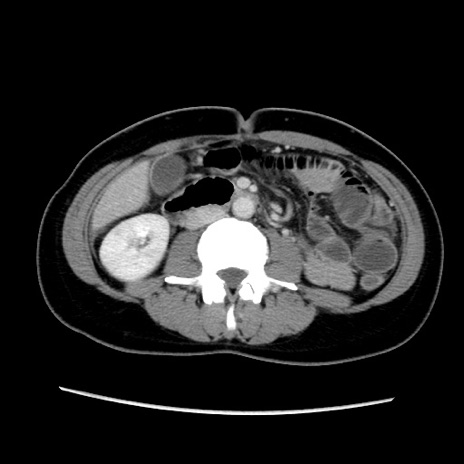

症例39(横断像)

【症例】40歳代女性

【主訴】上下腹部痛

【現病歴】2日目から下腹部痛あり。夜間は痛みで眠れなかった。昨日より上腹部痛と下痢が出現。臥位で痛みは軽快したため、休んでいた。本日になって臥位でも立位でも痛みが強くなってきたため救急要請。

【既往歴】子宮内膜症

【身体所見】部:平坦・軟、左上下腹部に圧痛あり、反跳痛あり。

【データ】WBC 21800、CRP 26.78